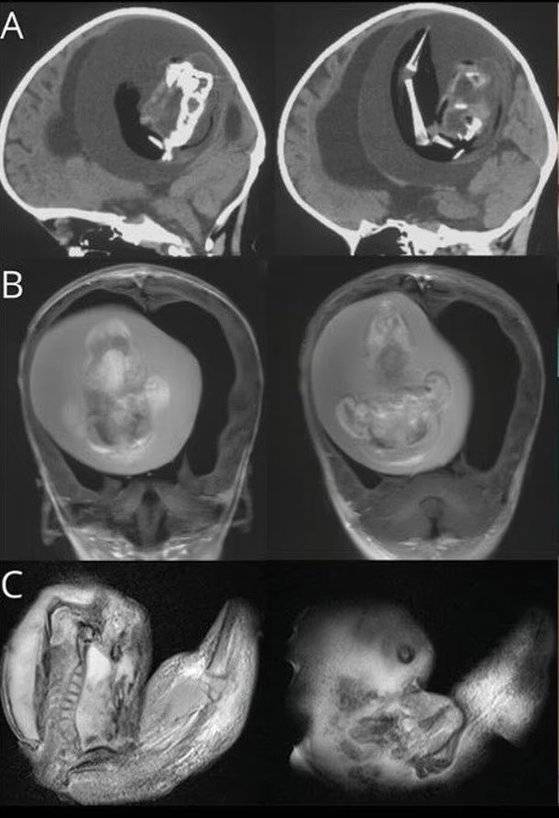

의료진은 아이 머리에 단순 종양이 있다고 판단해 CT(컴퓨터 단층 촬영)를 찍었고, 그 결과 아이의 두개골에서 뇌를 짓누르고 있는 쌍둥이 태아를 발견했다. 의사들은 아이가 두개골 속의 태아들에게 혈액을 공급했기 때문에 출생 후 1년 동안 계속 생존했다고 말했다.

아이는 두개골에 자리를 차지한 태아로 인해 뇌 일부분에 척수액이 고이는 수두증(물뇌증)을 앓았다. 수두증이 진행되면 머리 둘레가 비정상적으로 커지고, 극심한 졸음이나 발작을 일으킬 수 있다.

의료진은 아이의 두개골에서 즉시 기생 태아를 제거했다. DNA 분석 결과 해당 태아는 아이의 쌍둥이였던 것으로 조사됐다.